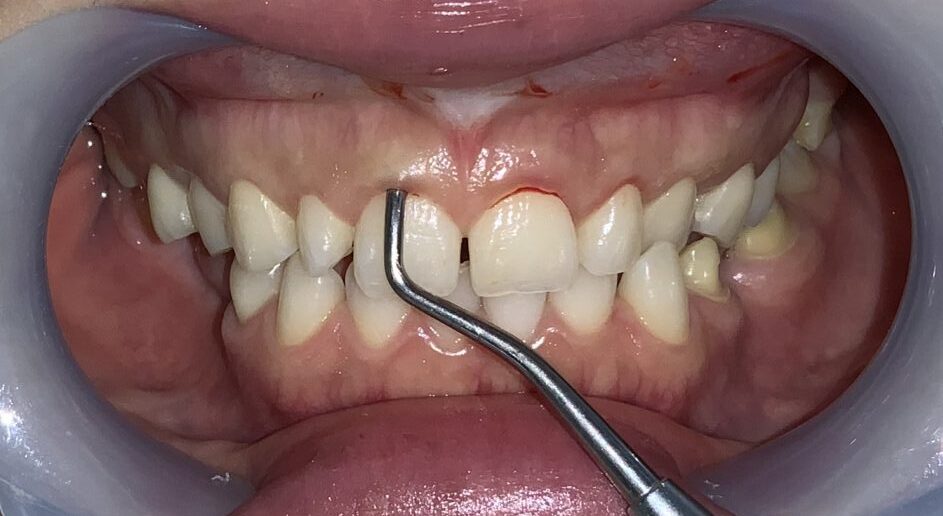

まずは前歯の2本を治療して、患者様に確認をして頂きました。

やはり、向かって右側(患者様の左側)の歯は歯槽骨が尖っている部分が認められます。

この部分ですね。

このままの歯槽骨状態では、後戻りをしてしまうので、歯槽骨整形を追加して治療します。(追加費用はありません。)